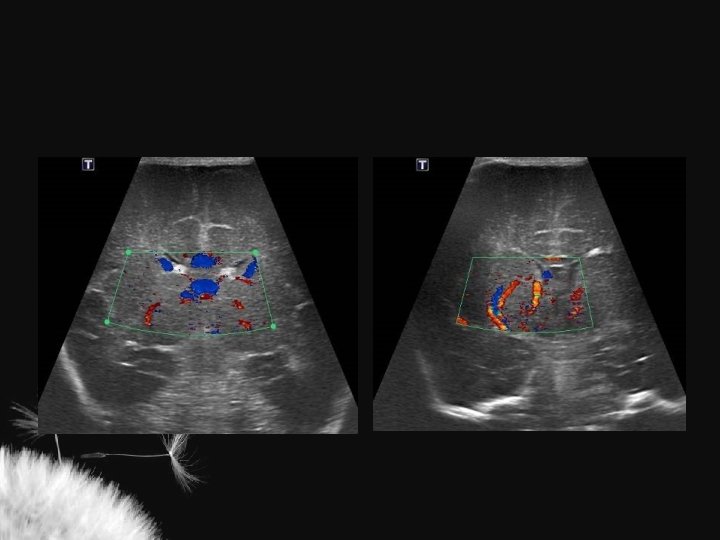

Macrocrania • Macrocrania benigna hidrocefalia benigna da infância, coleção extra axial benigna da infância • Condições patológicas: • US – Coleções anecóicas – Formato em V – Sulcos e giros proeminentes – Ventrículos normais ou proeminentes – Pia-aracnoide com ecogenicidade normal – Higroma subdural – Hematoma subdural – Abscesso secundário a meningite – Coleções ecogênicas – Formato em U – Sulcos e giros deslocados ou achatados – Ventrículos alargados – Pia-aracnoide hiperecogênica

Mc Cluney et al. AJNR 13: 1335 -1339 Chen et al. Radiology 201: 389 -392

Hidrocefalia benigna da infância – sinal da veia cortical positivo

Coleção subdural – sinal da veia cortical negativo